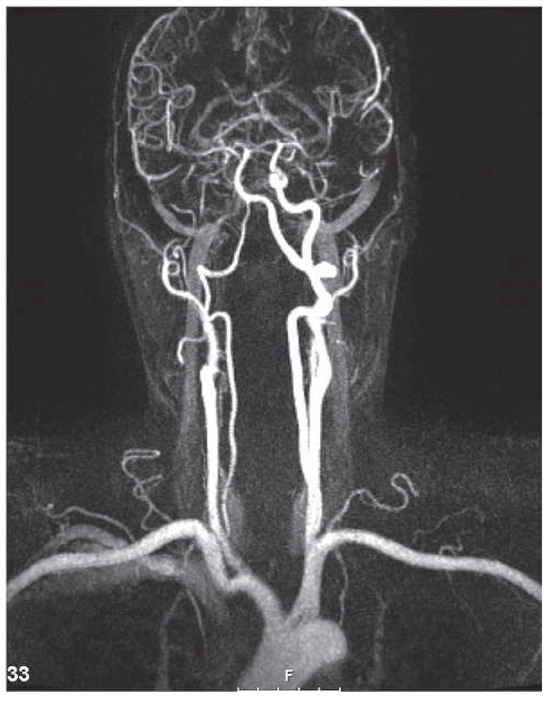

Dyspnoea and Impaired Ventricular Filling Due to Infiltration of the Left Atrium with a Lung Adenocarcinoma

by Federico Moccetti, Björn Müller-Edenborn, Walter Weder and Urs Eriksson

A 59-year-old patient without a history of heart failure complained of progressive dyspnoea of two weeks’ duration [...] Full article

Show Figures

Figure 1